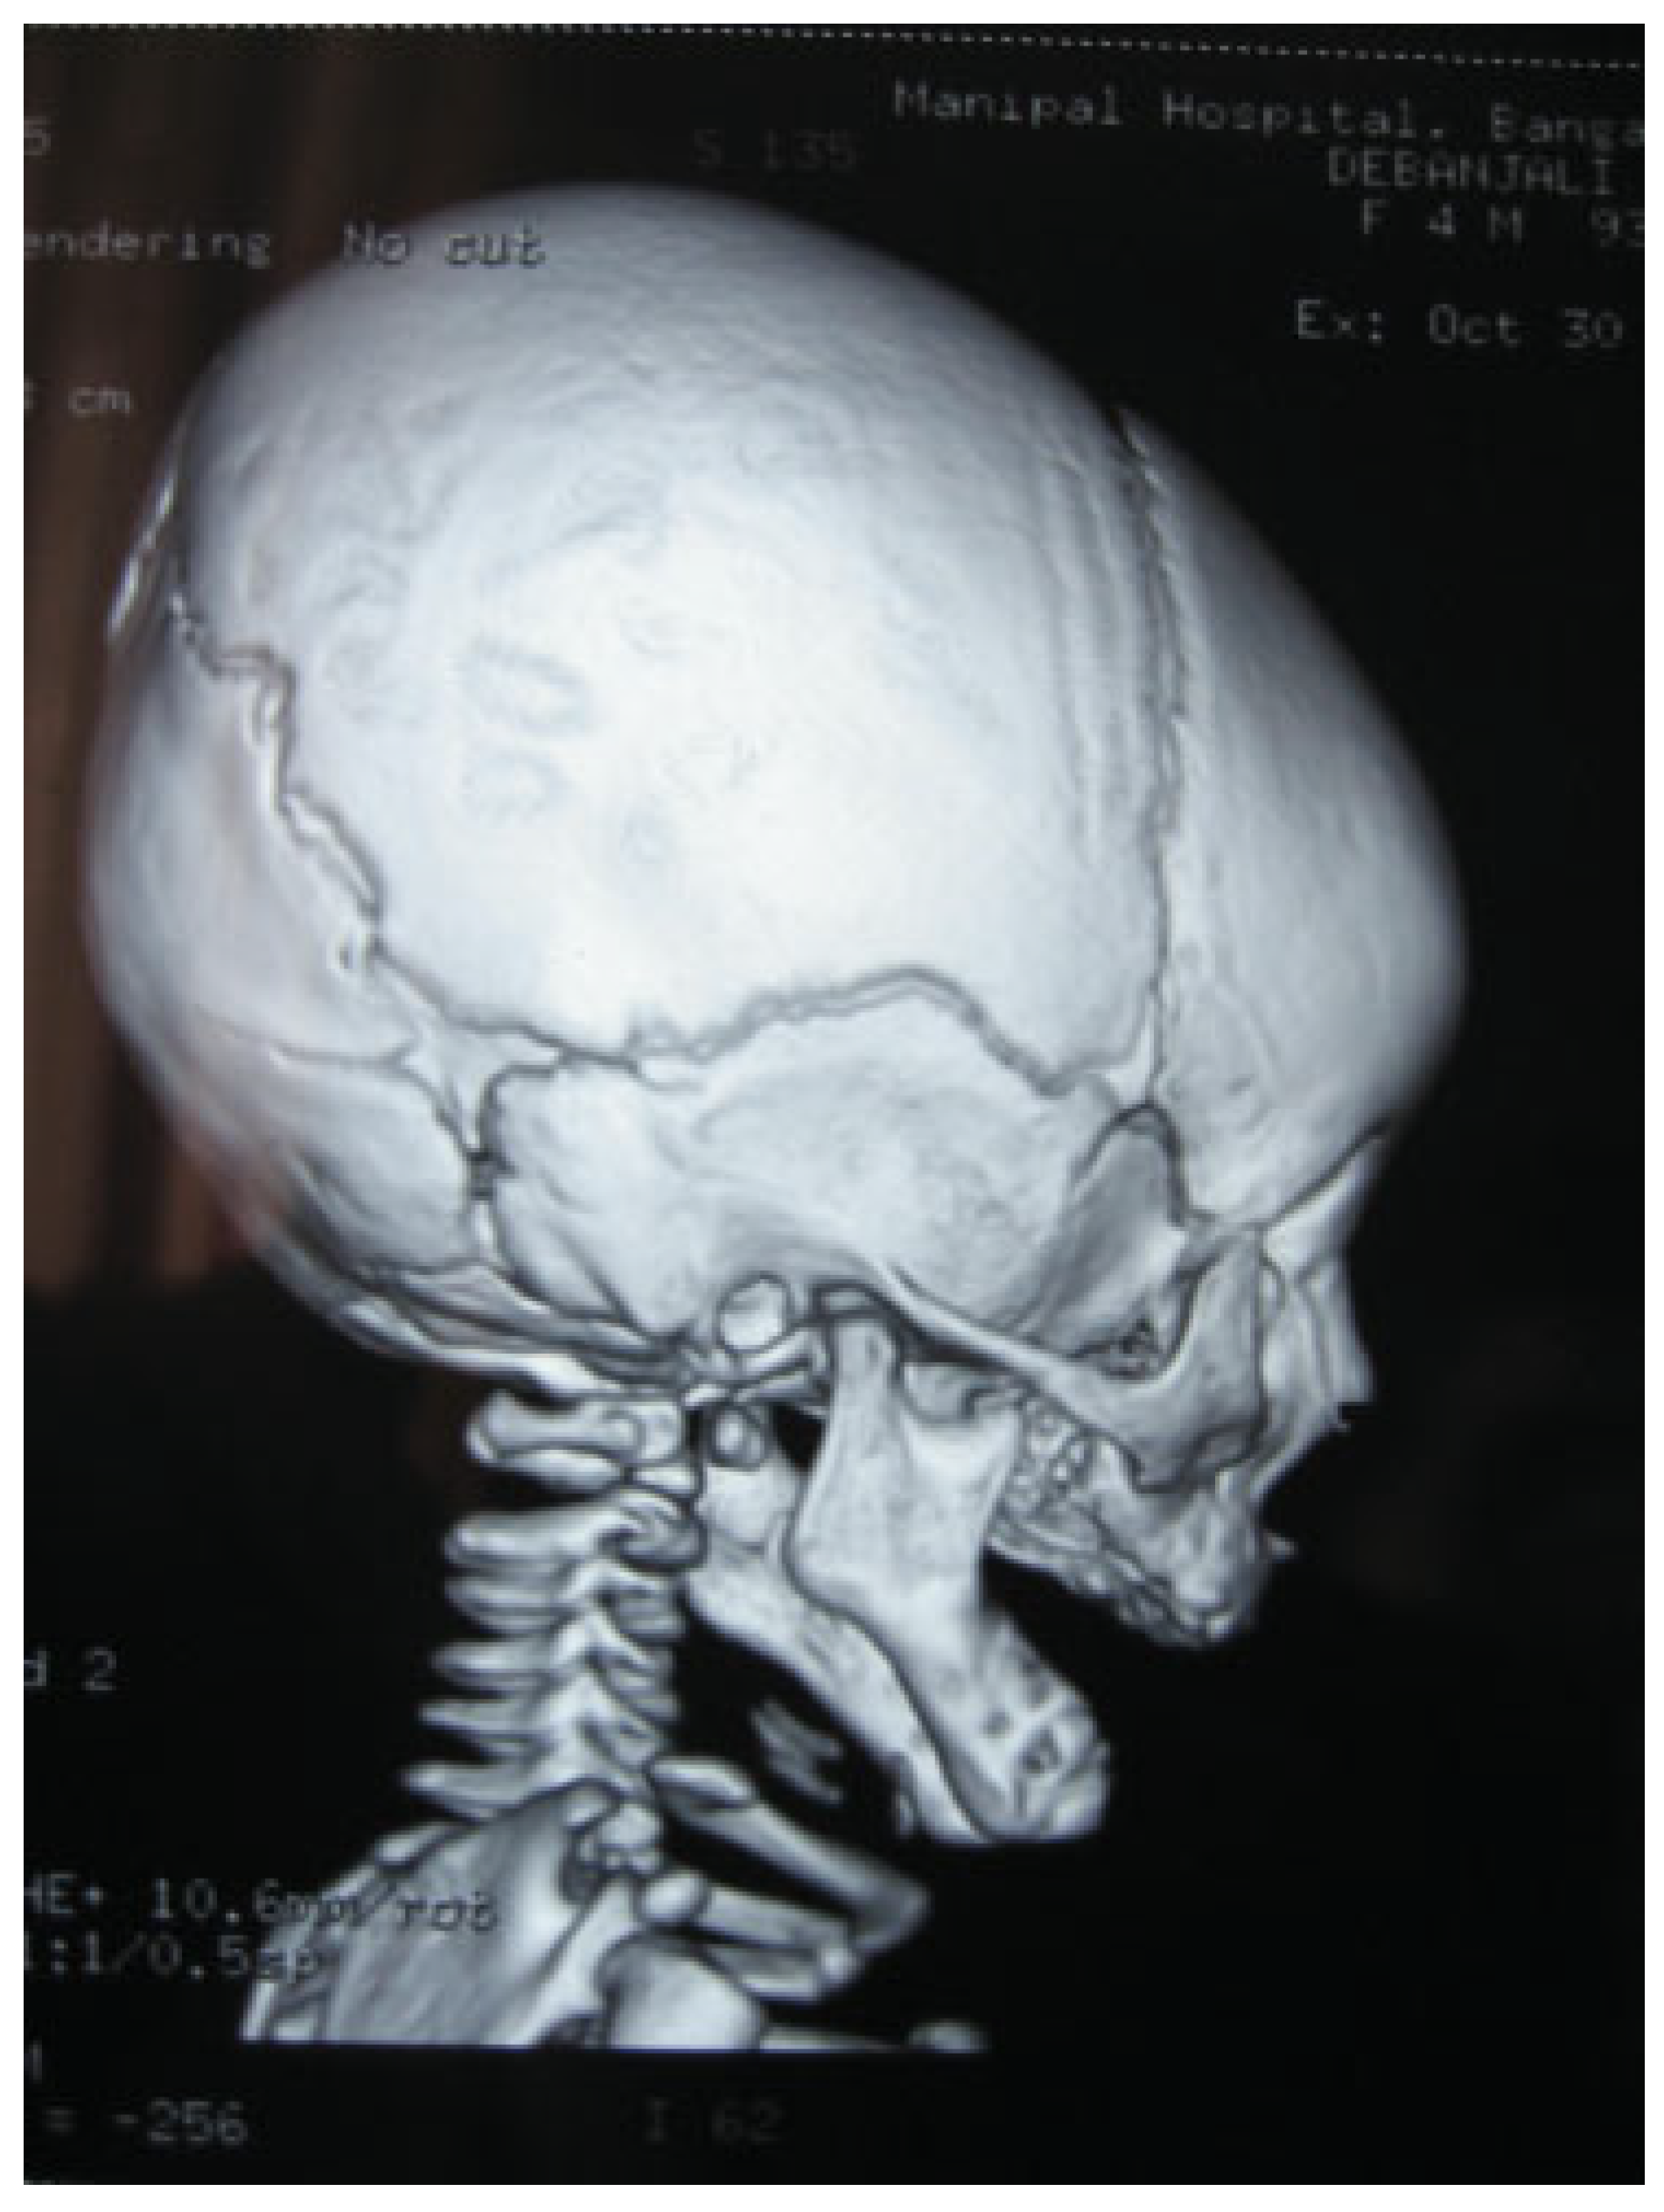

Complete Midline Cleft of Lower Lip, Mandible, Tongue, Floor of Mouth with Neck Contracture: A Case Report and Review of Literature

Case Report